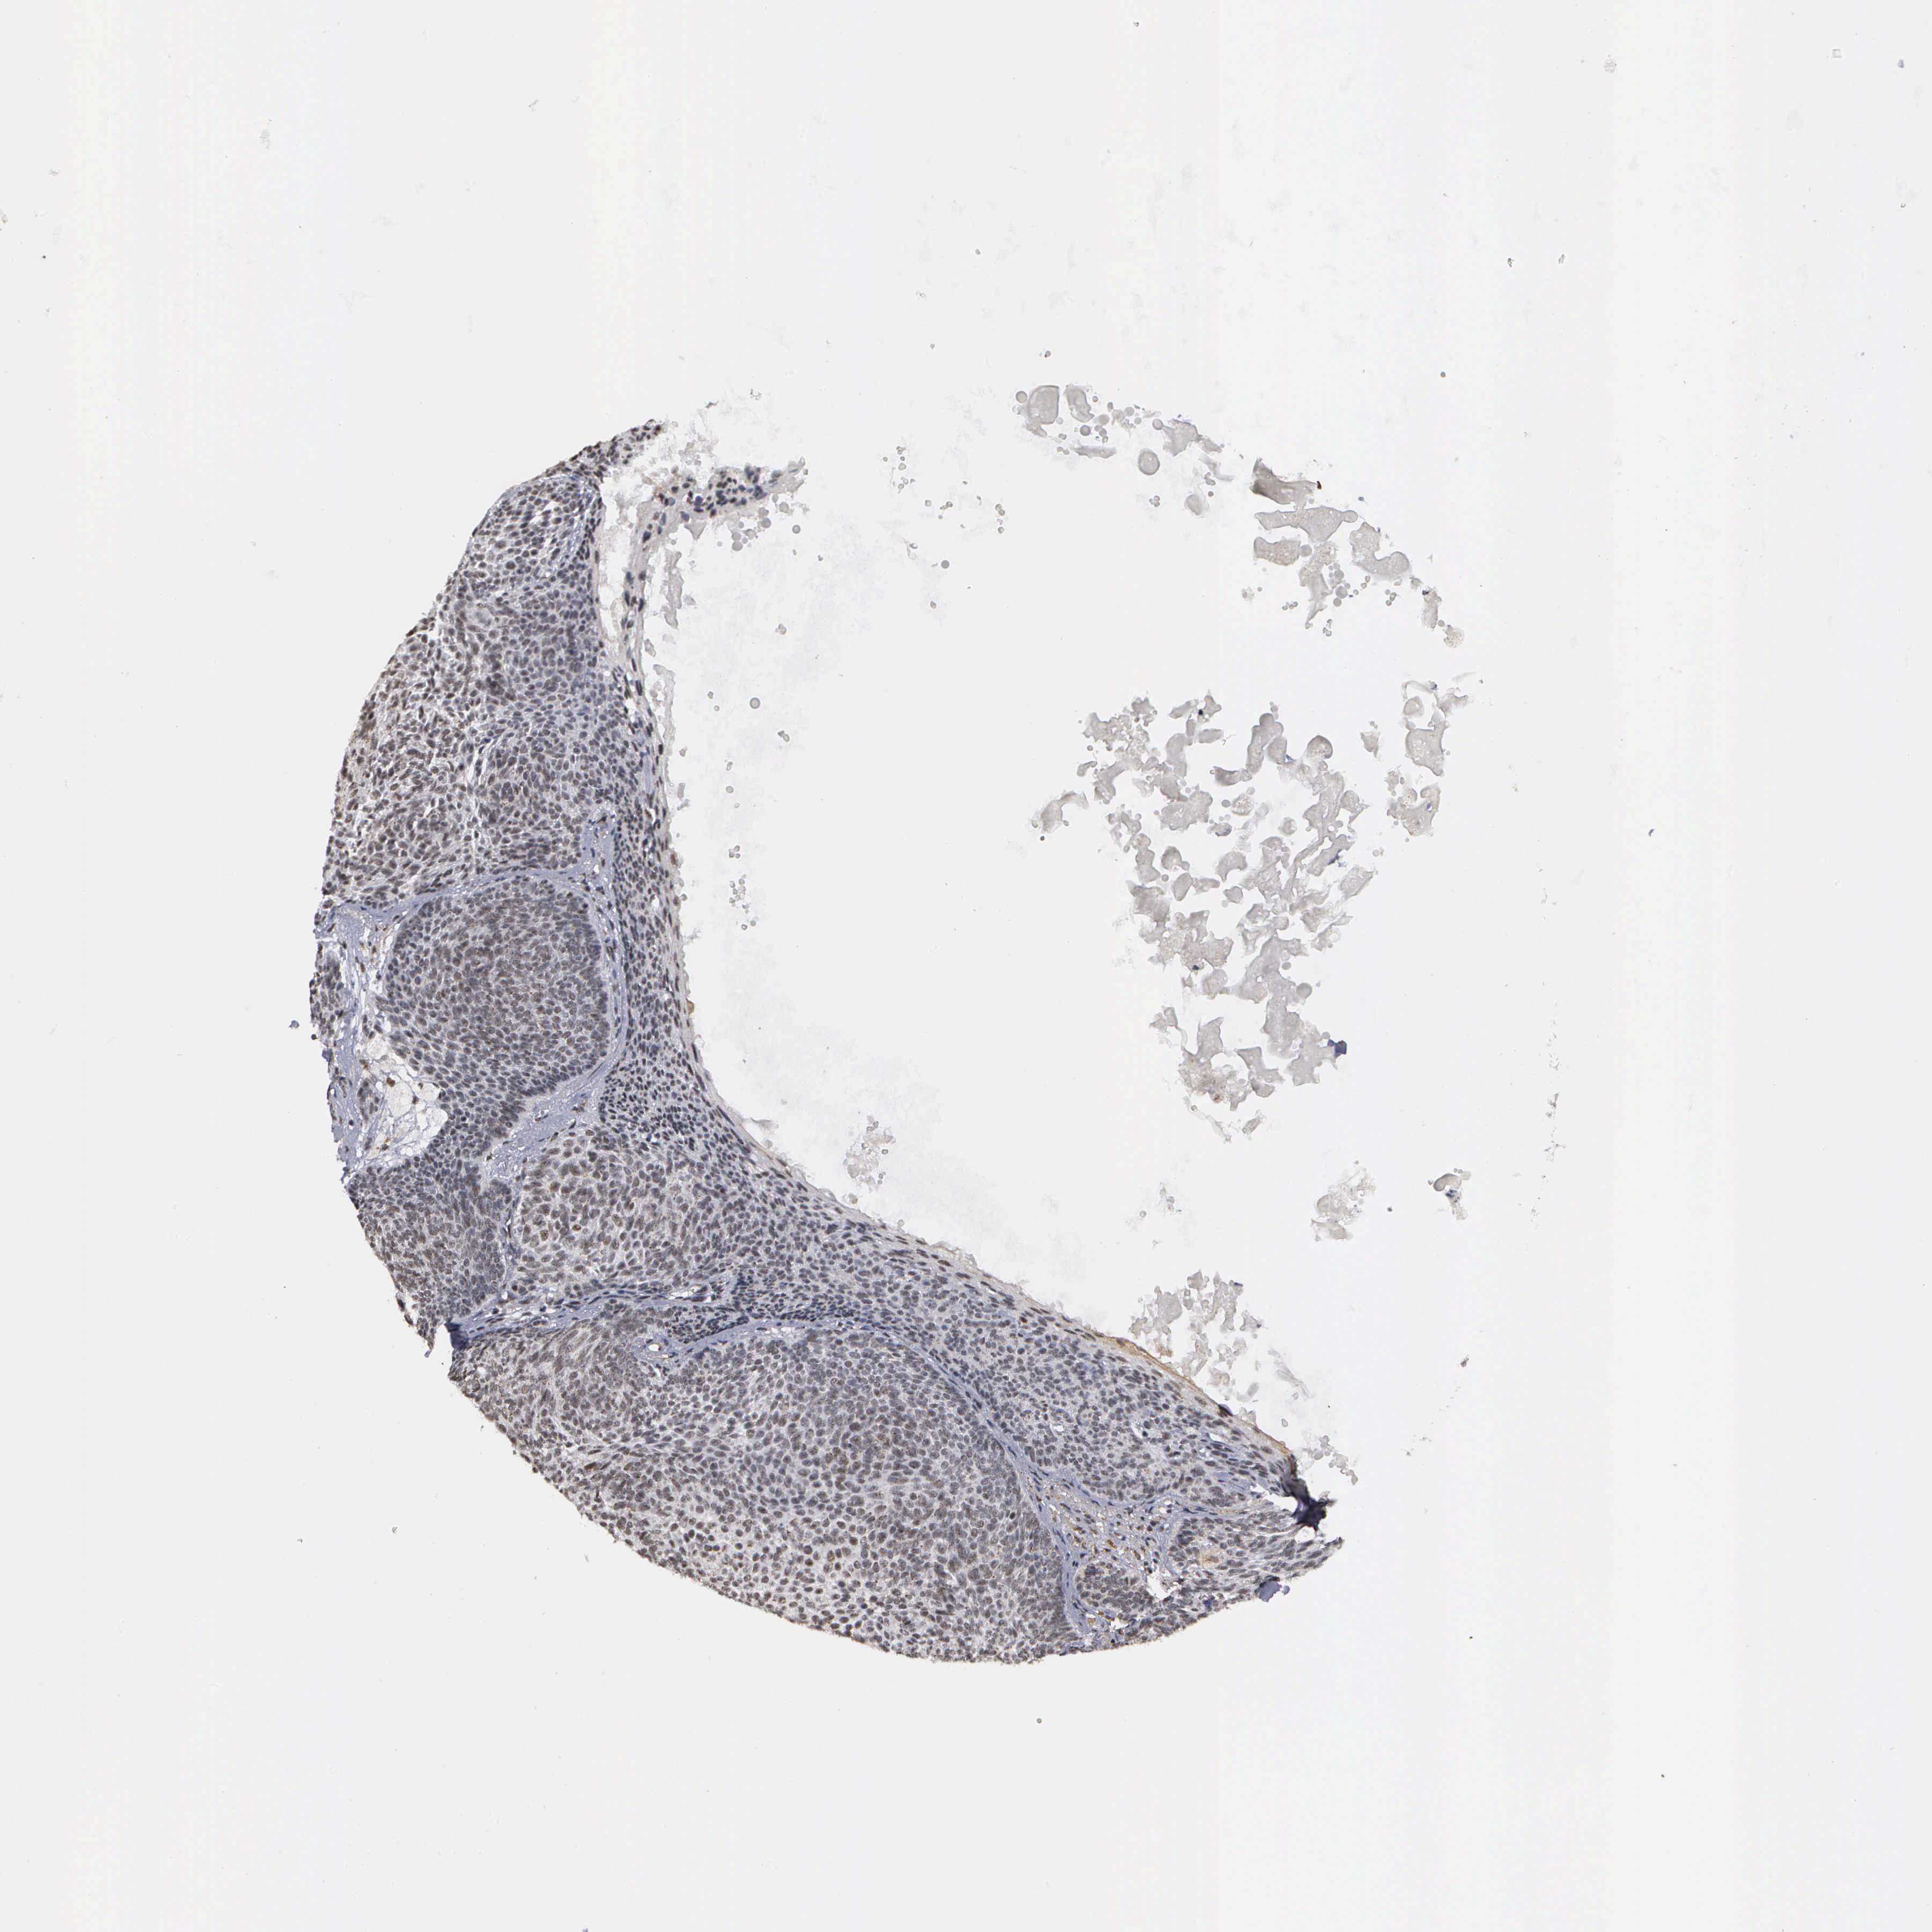

CANCER SKIN CANCER Show tissue menu

SKIN CANCER - Protein expressioni

A mouse-over function shows sample information and annotation data. Click on an image to view it in a full screen mode. Samples can be filtered based on level of antibody staining by selecting one or several of the following categories: high, medium, low and not detected. The assay and annotation is described here.

Each image is clickable and will lead to virtual microscopy that enables deeper exploration of all samples and also displays staining intensity scores, fraction scores and subcellular localization as well as patient and tissue information for each sample.

Antibody HPA000869

Staining

High

Intensity

Strong

Quantity

>75%

Location

Nuclear

Squamous cell carcinoma, NOS

Basal cell carcinoma